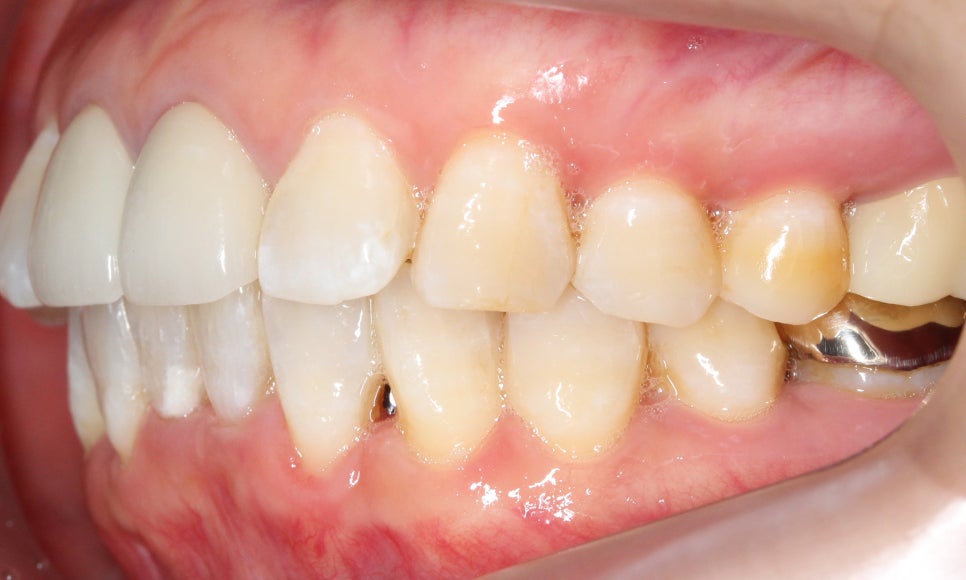

측면의 모습을 보면 아랫니의 앞쪽이

윗니의 뒷쪽으로 많이 들어가 있는 것을

확인할 수 있습니다!

반대쪽도 같은 모습인데요,

이렇게 아랫니가 윗니를 향해

깊숙히 물린다면 아랫니의 절단연에 의해

윗니의 잇몸이 상처를 입을 수 있습니다.

윗니는 아랫니에 비해

비교적 가지런한 모습이죠?

+앞니(중절치)가 약간 불투명하고

잇몸 부분이 까맣게 보이는 것은

보철치료를 진행하셨기 때문입니다!